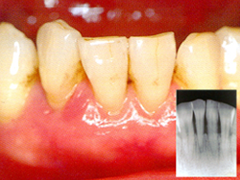

軽度歯周病

状態 : プラーク(歯の汚れ)が固まることによって、歯石となります。

症状 : 歯ぐきが赤くはれ上がり、ぶよぶよしてきます。骨が溶けだす場合もあります。歯ぐきから血やうみが出て口臭も強くなります。

治療法 : 外科手術(歯ぐきを切開して歯石やプラークをとる)や歯周再生療法(歯槽骨などの組織を再生する)が必要になります。